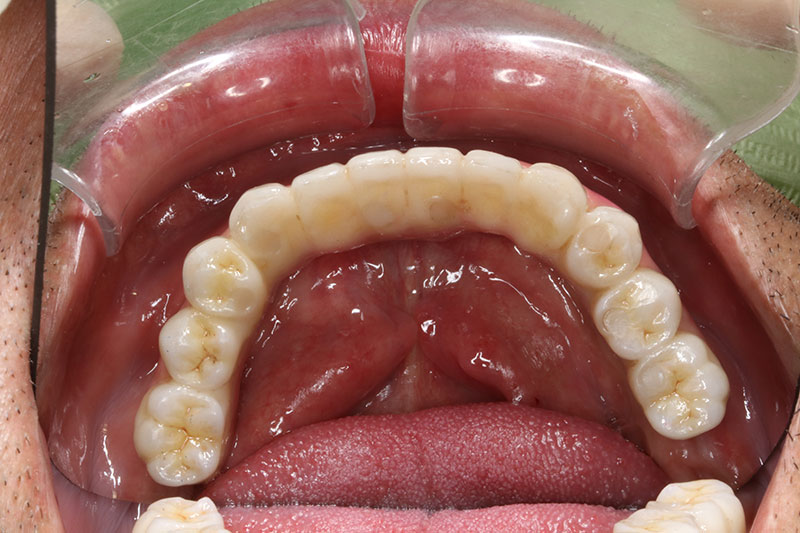

術後